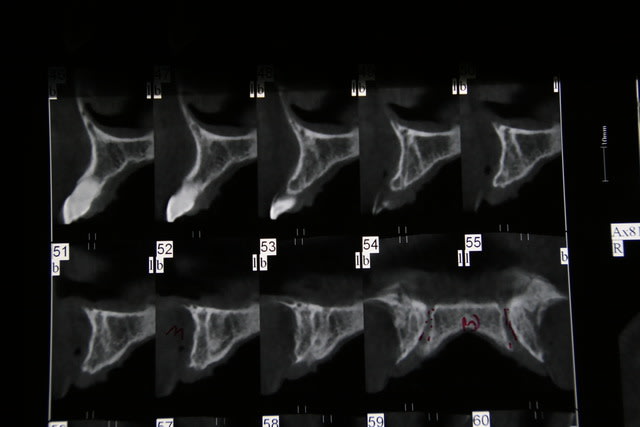

Salut ca y est je me lance, je compte deposé la 12 et 22 et implanter deux implants de 3,8*11. Je compte faire deux lambeaux distincts pour ne pas leser le foramen naso palatin, curetage curette et fraise , implant plutot palatin, assez enfoui , puis comblement bi ooss et mbne ossix, et enfin refermer le tout car pap deja présente pour 11 et 21.

Je n'ai pas bcp d'experience dans le secteur ant , qq implants au plus , ce que je crains c surtout la gestion des tissus pour refermer, si soucis vis cica pas loin...

si j'ai des osteotomes, je peux bien sur les utiliser mais j'ai peur d' etre guide vers l axe de la dent alors que j'aimerai partir plus palatin. quant au biomat c n 'est pas facturé..c juste pour combler le hiatus entre implant et cortic au cas ou l'os de forage ne suffirait pas.

Petit sondage parmi vous osteotome ou pas? Autre petite question si stabilité sup a 20 N : implants enfouis ou non ? Perso je pense les enfouir, mais j'espere pouvoir fermer hermetiquement ( incisions peiostées) le lambeau car je ne maitrise pas les lambeaux perdiculés ou les greffes epithélio conjonctives...

j'ai l'impression en fait que lorsque j'utilise mes osteotomes ,dans ces cas , je maitrise moins les axes ( c peut etre subjectif) ,que les corticales m'impose la place de l 'implant. En general je pointe a l fraise boule, foret pilote et je passe les differents diam . Et puis tu sais en omnipratique les implants ne sont pas quotidiens et donc tu as tjs tendance qd c possible a utiliser le mm protocole pour optimiser tes succés.

bon c fait ce matin , pose des deux implants 12-22, avec un axe un peu particulier dans le sens vestib palatin car proalveolie avec béance ant. J' ai utilise le foret pilote puis osteotome jusqu'a 3.8 de diam ( stabilité primaire 35 pour 22 et inf a 20N pour 12). J'ai fait deux ROG bio oss , ossix car malgré les avoir bien enfoui, la table externe etait vraiment trés fine. J'ai refermé avec difficulté pour trouver l'hermeticité notamment sur 22 ou la racine etait quasiment resorbée. PAP provisoire et feu ... reouvertue prévue dans 6 moi si tout va bien a suivre....